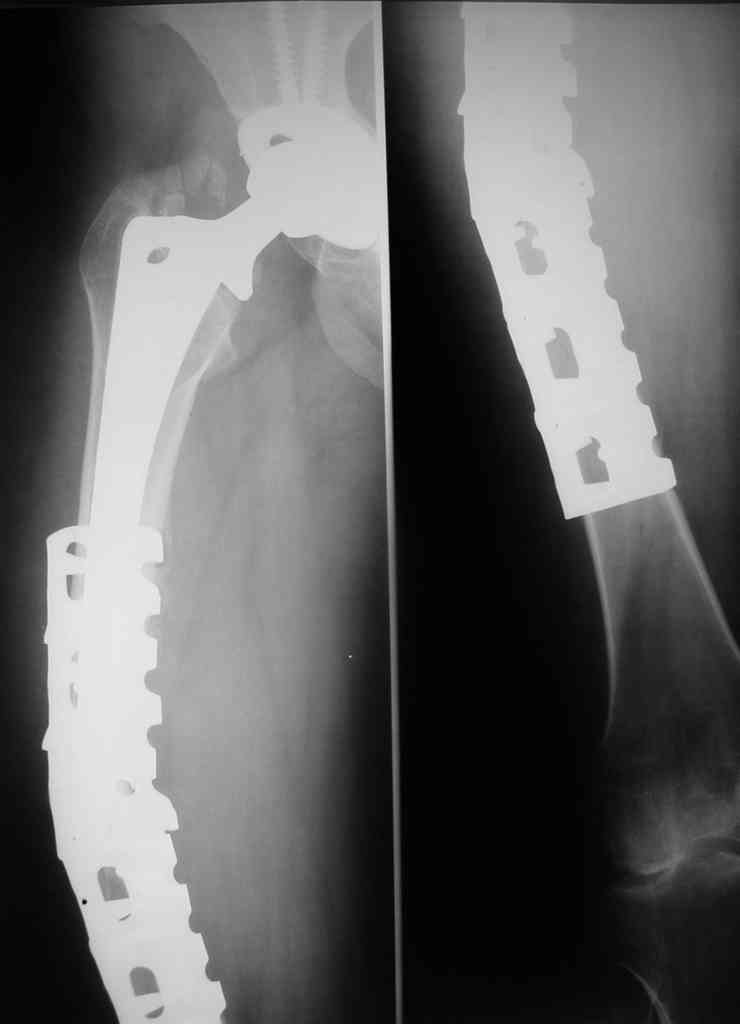

Zimmer distal femoral periarticular plate will follow contour of the shaft from distal femur to the troch. Use of 3.5 screws with round washers through the 4.5 plate allows a few long "uni" screws in the proximal fragment. Plate should go all the way to the trochanter. Distal fixation will not be a problem. Avoid anything circumferential near the fracture site. Bone grafting + / -, more important to let the quad reattach to as much of the femur as possible and provide stability with a VERY long plate.

Revision arthroplasty requires a long troch osteotomy and further compromise of the vascularity at the fx site. Even a 10 inch stem at revision might not satisfy the mechanical requirements of the shaft fx.

I would try a repeat fixation as above.

This depends on the stem fixation. If the stem is fixed then it's a Vancouver type B1 fracture and should be fixed with a plate well past the Fx and at least 2-3 shaft diameters above the Fx site proximally (fixed with cerclage wires proximally).

I'd remove that bridging plate device and just use a long locking plate with autologous bone grafting. Cortical strut grafts are not necessary, as it looks like the plate has failed, not the bone.

redo fixation is my choice as well, but, I do not use this plate and would not use it again. try

Locking plate with cables proximally, plus screws and screws distally.

В данном случае можно порекомендовать обычную блокированную пластину для накостного остеосинтеза бедра. Над проекцией ножки протеза лучше всего использовать специалаьные перипротезные блокированные винты, длиной 12-18 мм, в зависимости от толщины кортикального слоя. Если толщина кортикала недостаточна и возникает конфликт винт-ножка протеза, то вместо винтов в отверстие пластины можно установить специальный держатель серкляжа, через который проводится проволока.

Делать специальные пропилы для проволоки на пластине мы не рекомендуем, т.к. мелкий паз проволоку не удержит, а глубокий ослабит пластину. При выполнении же повторного остеосинтеза в данном случае можно предположить, что переостальное кровоснабжение критично нарушено, эндостальное тоже недостаточно, следовательно консолидация произойдёт в заведомо более длительный срок, тем более искуственно ослаблять конструкцию не желательно.

Приминительно к данному случаю LC-LCP широкая пластина на 14-16 отверстий под винты 4.5/5.0. Над ножкой 4-5 блокированных перипротезных винтов или их комбинация с держателями серкляжа. В дистальном отделе 4-5 блокированных или кортикальных (или их комбинация)винтов. В зоне перелома стягивающий кортикальный винт, либо можно вообще не использовать винты.

Всё это справедливо только при условии если сохранена стабильность ножки протеза.

The correct ORIF is with a LCP system with a good fixation either proximally or distally (longer than this one).

I think that in this case I'll add also bone graft because that plate damage the bone under the plate.